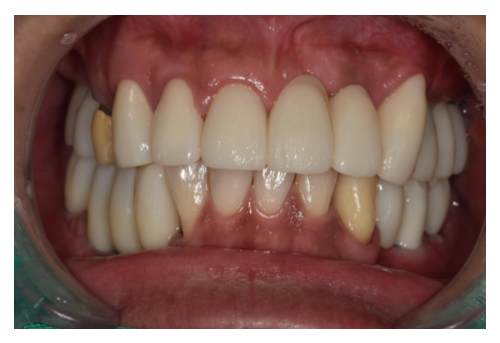

충치치료

1 치과공포증 치료 케이스

안녕하세요.대표원장 손승환 입니다.오랫만에 블로그 글로 인사드리는 것 같네요.요근래 환자분들이 많이 찾아주셔서 너무 정신없..